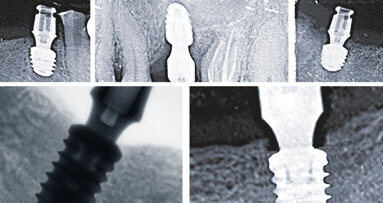

First of all, if you submerge the implants into 1-2 mm of bone, you achieve better results. In implants with a backtaper design, it is possible for the bone to grow into the space created in the upper part of the implant. This physically increases the resistance of the implant to lateral forces and reduces the risk of bone resorption. Additionally, if you can create sufficient keratinised soft tissue around the bone, the long-term success of the implant will be guaranteed.

If the implant is positioned 1-2mm subcrestally, the bone chips placed on it can act as scaffold and give support to new bone formation. Thus, preventing the ingrowth of the soft tissue.

All these design concepts complement one another and provide extra advantages for the longevity of the implants. When abutments are placed on the implants, they provide a narrower fit than the implant diameter, fostering the Platform-Switch concept. With this design, zero bone loss can be achieved, but it is the backtaper implant/bone relationship that actually promotes bone growth.